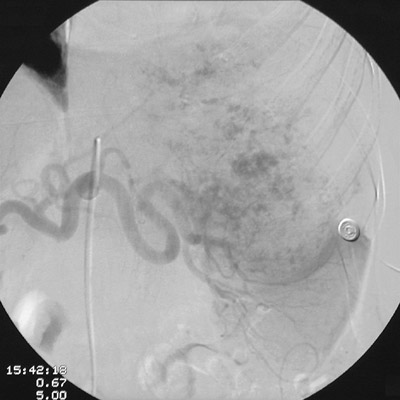

With injection of contrast into the celiac axis from the aorta, the angiographic views above and below demonstrate a vascularized mass involving the spleen. This is an angiosarcoma.